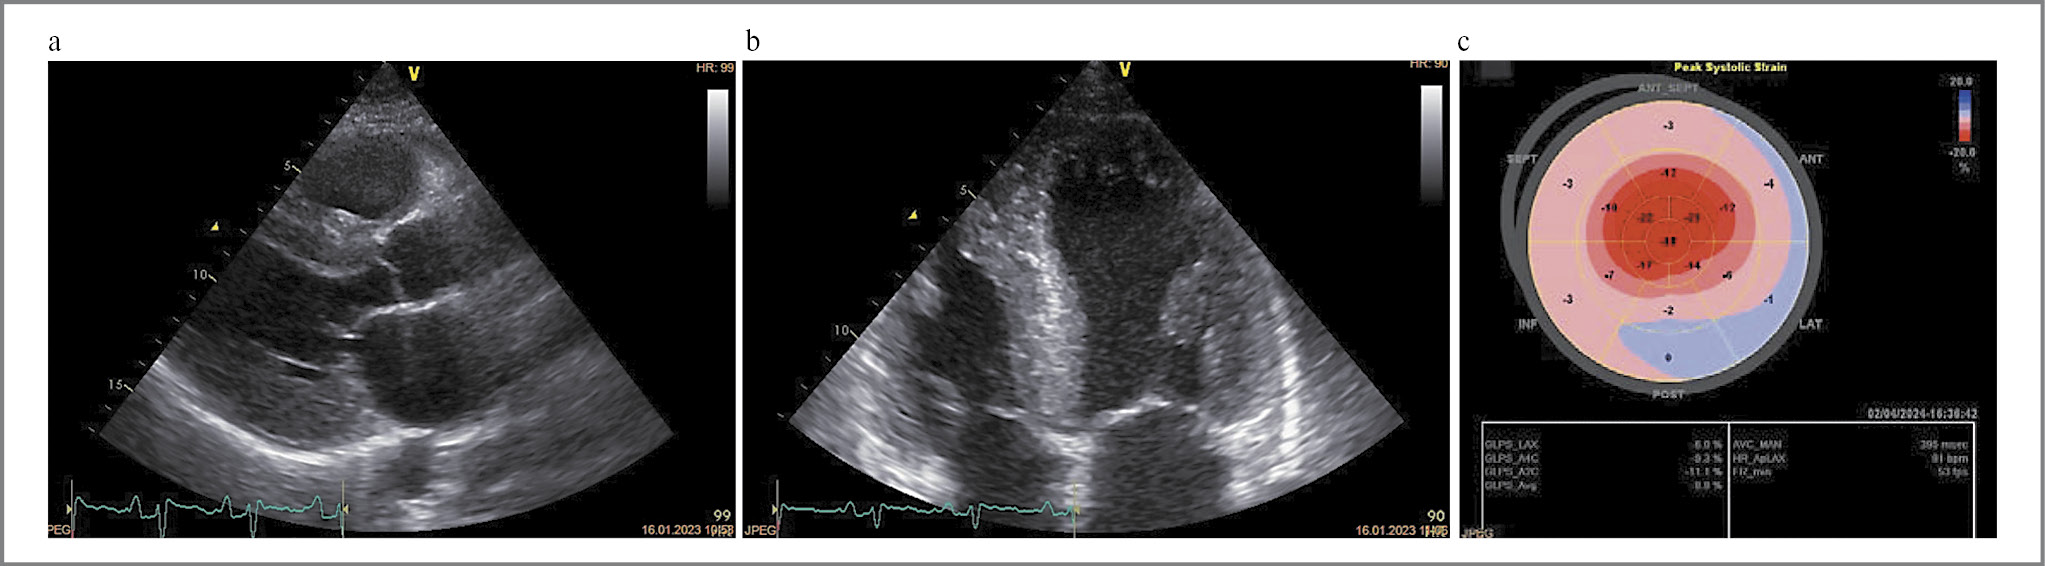

Рис. 5. Клинический пример 3. Пациент М. с AL-амилоидозом ГФ: a–c – выраженное утолщение стенок миокарда ЛЖ с характерным паттерном нарушения глобальной продольной деформации ЛЖ.

Fig. 5. Clinical case 3. Patient M. with HP AL-amyloidosis: a–c – pronounced thickening of the LV myocardial walls with a typical pattern of impaired LV global longitudinal strain.

Главным образом встречалось сочетание ГФ+РФ (43%) (рис. 4) и ГФ (30%) (рис. 5). У 1 (1,8%) пациентки присутствовал истинно РФ, характеризующийся дилатацией полостей предсердий, выраженным нарушением диастолической функции миокарда ЛЖ по рестриктивному типу при отсутствии утолщения стенок ЛЖ более чем 1,2 см (рис. 6).